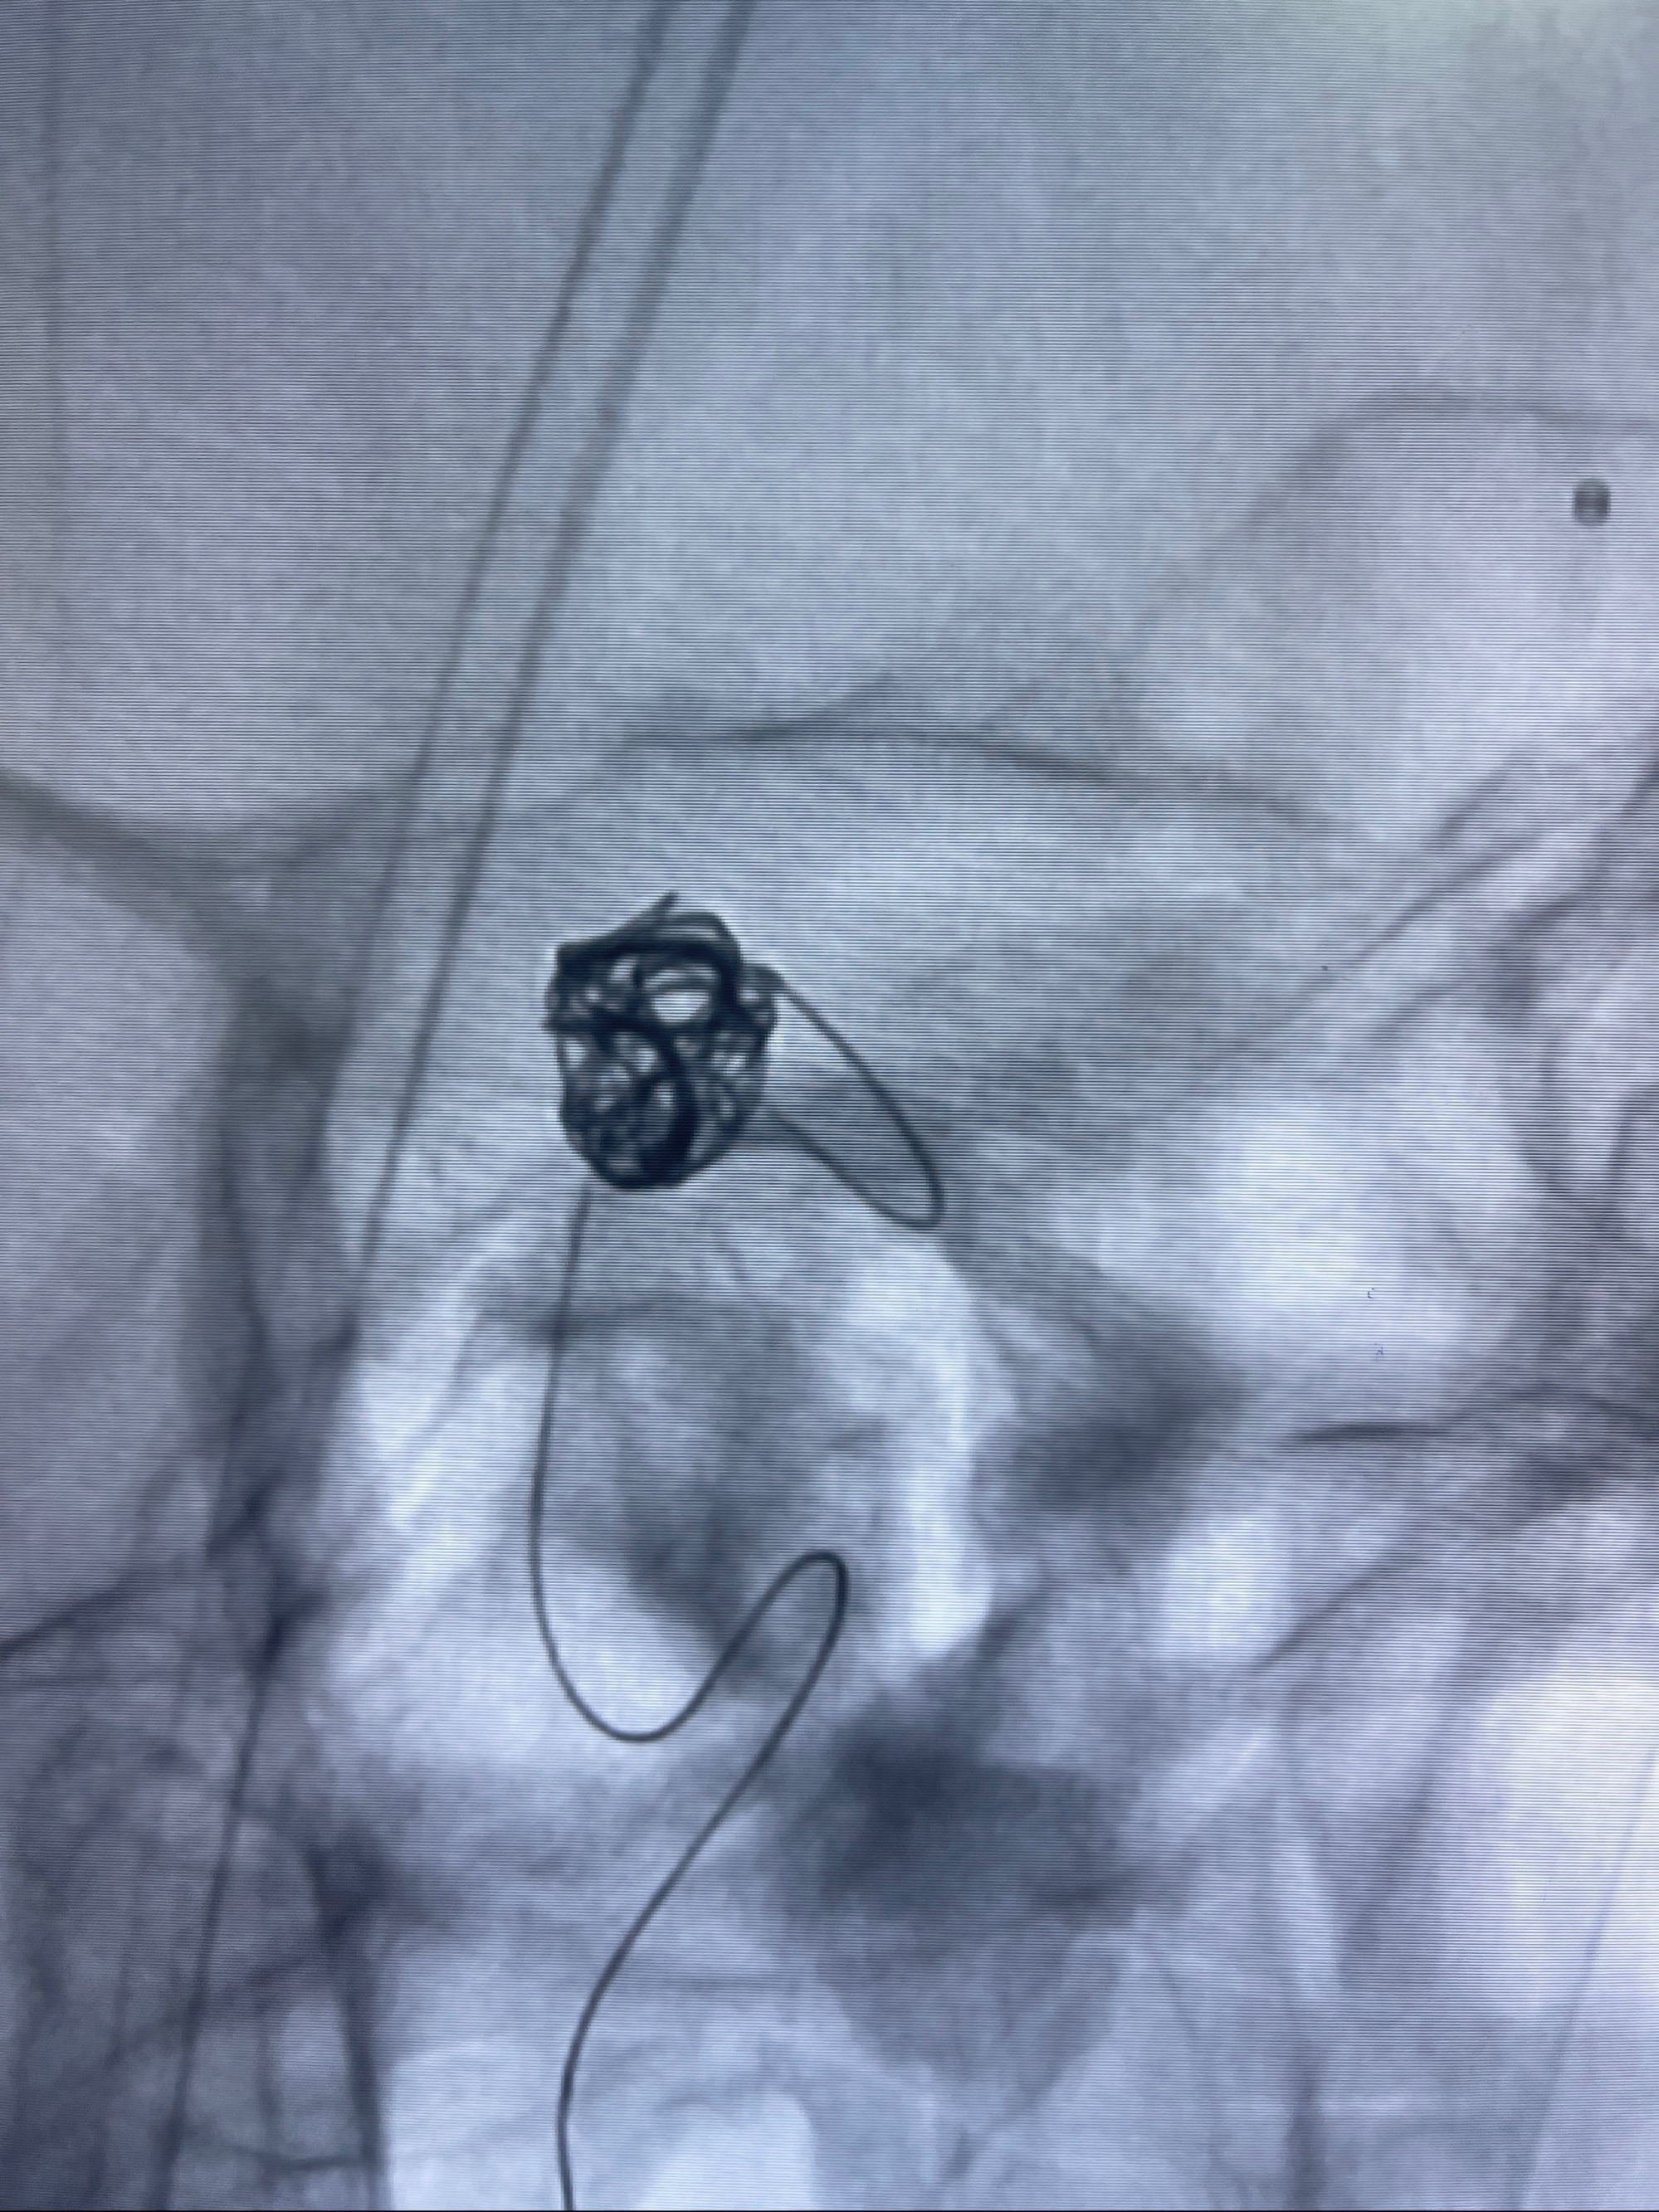

- Tubridge 4.0-20mm密网支架

- 加奇微弹簧圈:7*30/6*20/5*20/2*8

术后3D显示支架贴壁佳